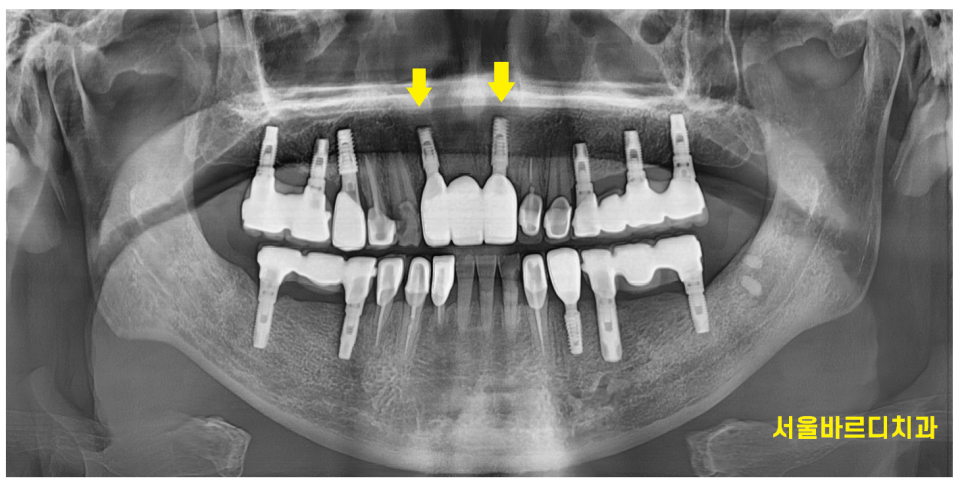

< 완성 사진 >

240312

치료 후 처음에 브릿지 치료로 안한게

참 다행이다 생각이 들었던 것이..

처음 넘어지면서 부러진 앞니 옆 치아에도

충격이 갔었던 모양입니다.

치료를 끝내드리고 6개월정도 지나

옆에 치아가 부러져서

현재 임플란트 치료 진행중입니다.